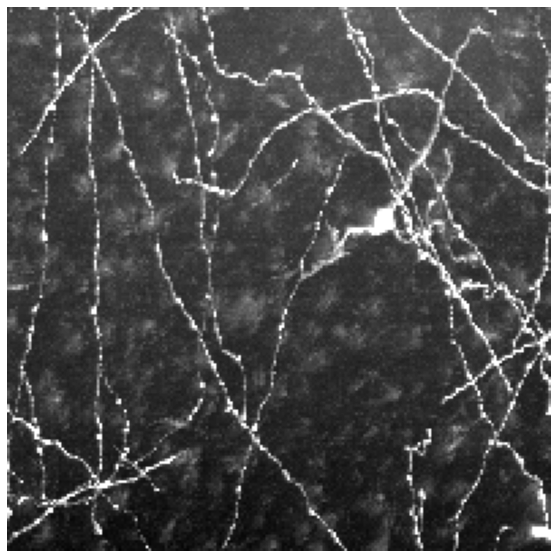

We tested our approach on three data sets. The Brain comprises 14 light microscopy scans of mouse brain, sized . We use 10 of them for training and 4 as a validation test. Neurons contains 13 light microscopy scans of mouse neurons, sized . We use 10 for training and 3 for validation. MRA is a publicly available set of Magnetic Resonance Angiography brain scans [3]. We crop them to size by removing their empty margins, and use 31 annotated scans for training and 11 for validation. A sample image from each data set can be found in Fig. 4.

| Brain | Neurons | Neurons | MRA | |

|---|---|---|---|---|

| Input | ![]() |

![]() |